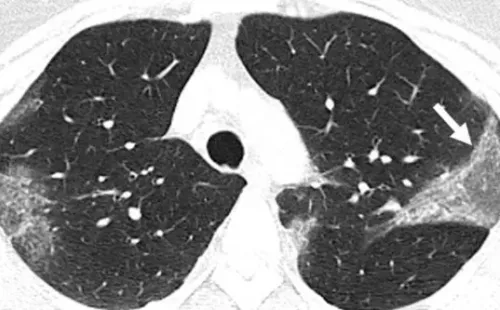

La explicación al riesgo que ellos tienen se debe a la acción de dos procesos: El primero con relación al pulmón, ya que se forma una mucosidad por la respuesta inmune al SARS-COV2, generando un aspecto que se conoce como Opacidad en Vidrio Esmerilado (ver imagen de abajo).

Imagen de Radiological Society of North America.